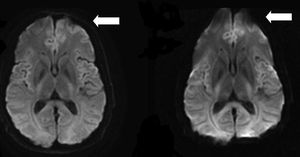

(left) High rBW = 250kHz, (right) Low rBW = 62 kHz; both at 3T field strength. Distortion is highly reduced using high bandwidth. The unit of the receiver bandwidth can change between vendors, as peak to peak or Hz/pixel, and lead to mistakes if protocol parameters are copied without proper adjustment (de Figueiredo et al 2011).